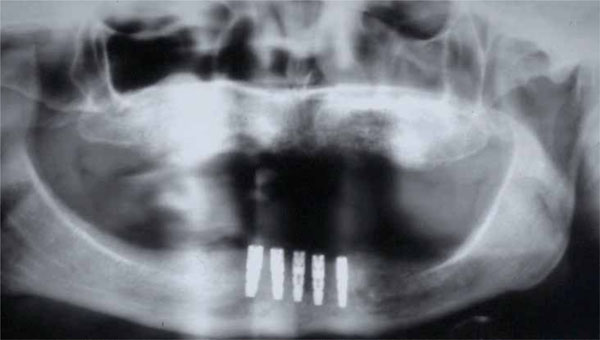

Before surgery, partially edentulous patients received proper oral hygiene instructions and oral hygiene treatment. At the end of the initial therapy, before starting the surgical procedures, the patients demonstrated proper plaque control. All patients underwent radiographic exams prior to surgery (Figs. 1 and 2).

Fig. (2).

Clinical situation before surgical procedures.